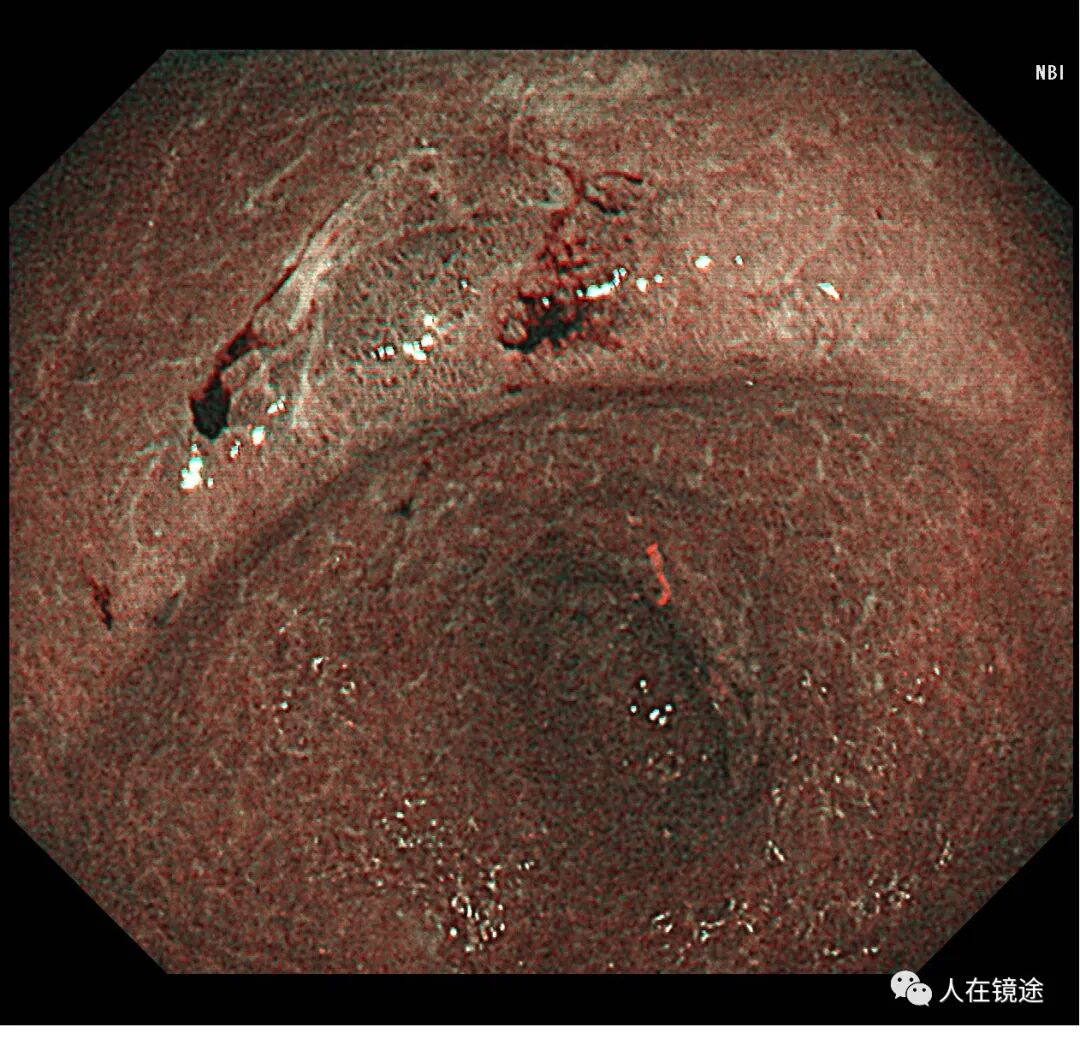

NBI示:胃窦小弯见一0.8*1.2cmIIa粘膜病变呈咖色,边界清楚,表面粘膜高低不平伴自发性出血。